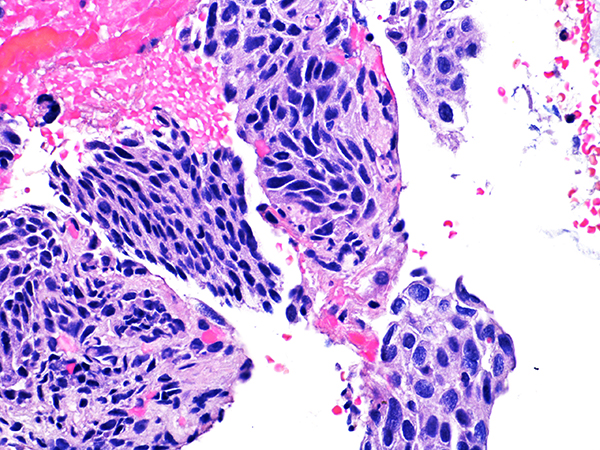

Case 2

Soft Bx CIN 2

40x - High Power